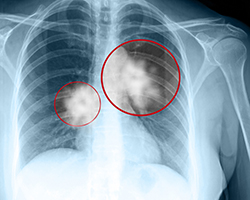

The Michigan Department of Health and Human Services has announced the availability of a new Lung Cancer Screening Communications Toolkit. The toolkit has ready-to-use items to help promote lung cancer screening to Michigan residents, physicians, and public health partners including a sample newsletter article, press release, and social media posts; digital files for use on websites, social media, or with newsletter articles; and lung cancer facts and data resources.

The lung cancer screening test is for current or former heavy smokers between the ages of 55-80 years of age. In Michigan, the American Cancer Society estimates that there will be 8,440 new cases of lung cancer, and 6,030 deaths due to the disease in 2016. To aid Michigan residents, the Michigan Department of Health and Human Services is asking members of the Michigan State Medical Society to support these cancer screenings.